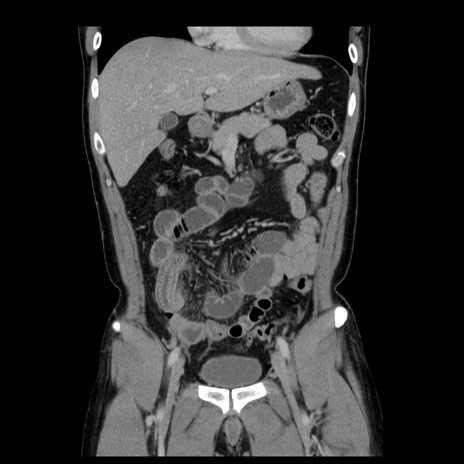

症例4(冠状断像)

【症例】30歳代男性

【主訴】腹痛、嘔吐

【現病歴】昨晩から突然の腹痛あり、その後嘔吐、軟便も出現。腹痛が改善しないため救急搬送となる。2日前にしめ鯖の食事歴あり。

【身体所見】意識清明、苦悶様、BP 135/90mmHg、BT 35.7℃、腹部:平坦、やや硬、心窩部〜臍部に自発痛、圧痛あり、筋性防御+、反跳痛-

【データ】WBC 8100、CRP 0.57